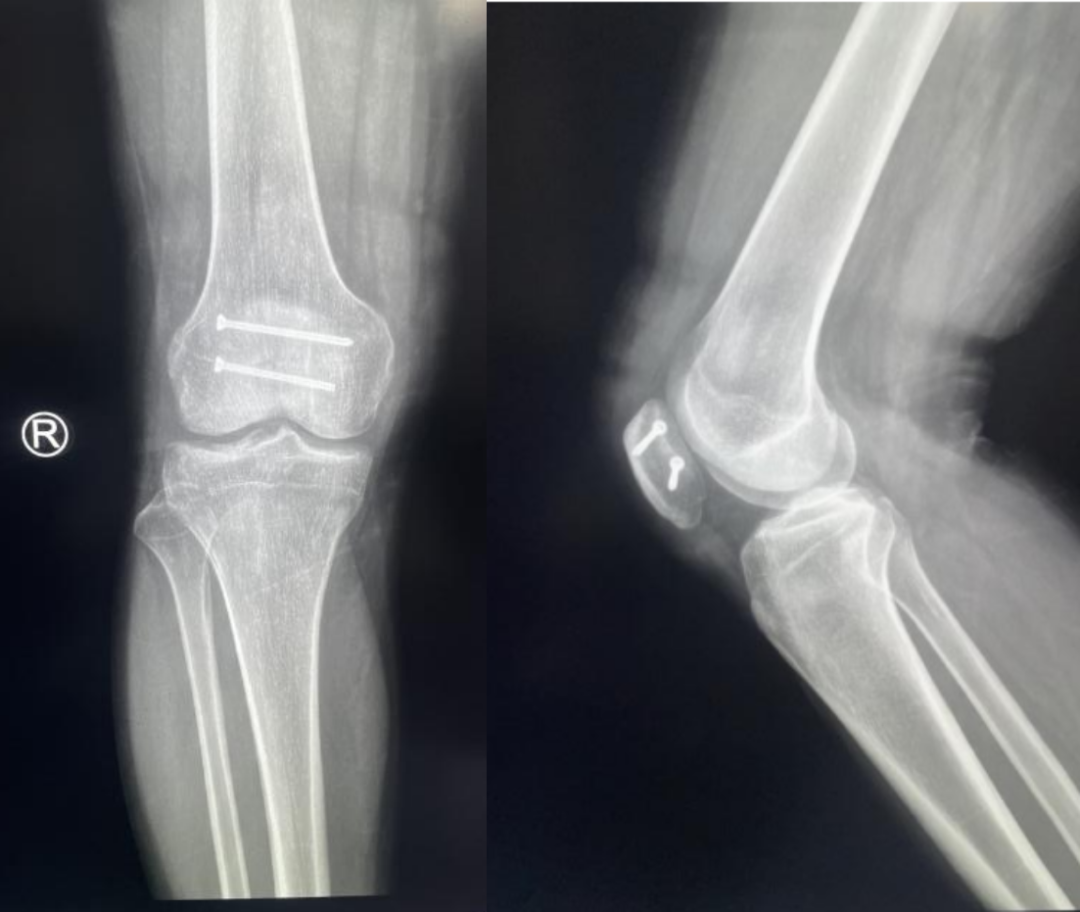

髌骨骨折正侧位  图源:作者提供

除以主诉和典型体征外,膝关节 X 线片也是必不可少的一项辅助检查,以膝关节正侧位 X 线片最常见,如果怀疑纵向骨折,膝关节屈曲 45° 时髌骨 30° 切位片可以辅助诊断。

完全关节内骨折克氏针加张力带固定  图源:作者提供

克氏针加张力带钢丝;有第三个骨折块则采用拉力螺钉或克氏针加张力带钢丝固定;对于 4 个或 4 个以上的骨折块采用克氏针加螺钉加张力带钢丝进行固定;对于严重粉碎和软骨面广泛破坏的髌骨骨折,髌骨部分或完全切除也是一种可行的办法。